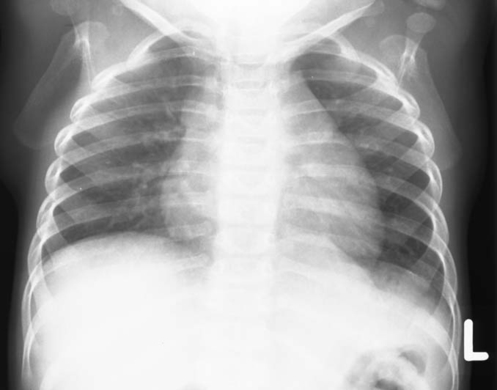

3: Lungenröntgen eines Neugeborenen

thoraxu _3_.jpg

Download Photo (497 x 390)

Datum: 25.06.2004

Betrachtungen: 49